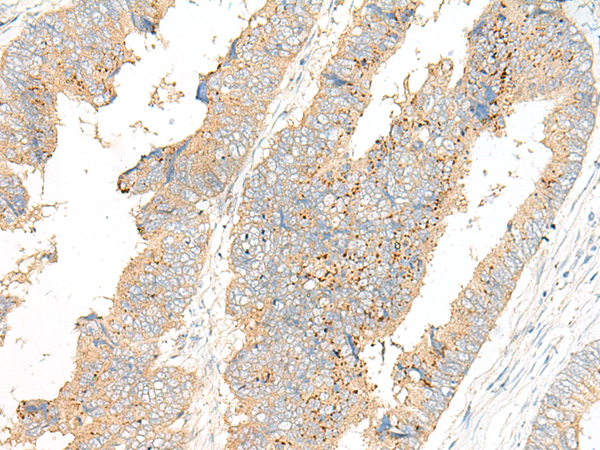

IHC positive control:

Human colorectal cancer and Human cervical cancer

IHC Recommend dilution:

25-100